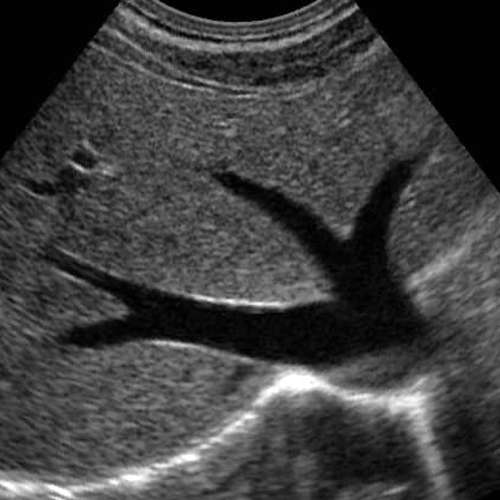

We have a huge number of cases with different modalities and regions

By Modality